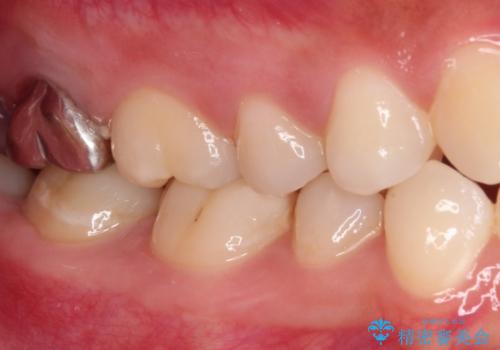

- 奥歯の銀歯に不快感が続くとのことで来院された患者様です。

銀歯の適合が悪く、汚れが溜まりやすくなっており、更には根尖の病変が認められ、咬合時に痛みがありました。

親知らずの存在により、歯肉が歯を覆っているため、親知らずの抜歯により清掃性を改善し、根管治療により痛みを取り除くこととしました。